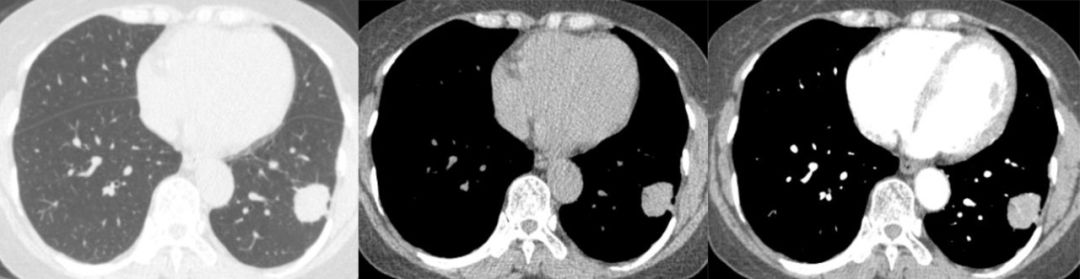

影像检查主要以 CT 平扫 增强为主

胸腔内实性肿块,与胸膜宽基底相连

孤立性肿块,边缘清楚光整,浅分叶

病灶发现时一般较大,直径达 8 cm 以上 医学百科网 | YxBaike.Com

密度较均匀,增强后均匀中等强化;病灶较大时可密度不均匀,增强后地图样强化 医学百科网 | YxBaike.Com

肿瘤内可见迂曲血管影及假包膜,少数病灶可见胸膜蒂

CASE 4 50Y/F 发现右肺占位 10 余天